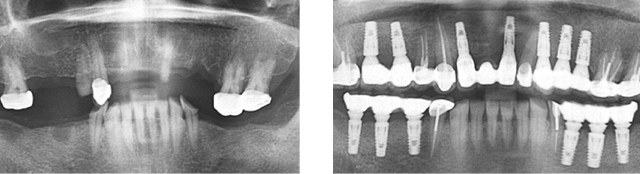

오래된 브릿지가 떨어지고 치아 결손이 심한 상태로 내원한 고혈압 환자분. 혈압이 정상 수치보다 높아 내과와 연계하여 혈압을 90~140 사이로 조절하여 총 13개의 임플란트를 식립 하였습니다.

고혈압의 경우 복용하시는 약이나 혈압, 혈당수치로 인하여 지혈이 어렵거나 면역력이 약해져 있어 수술 시 의료진의 노하우와 내과진료 연계가 가장 중요한 부분입니다.